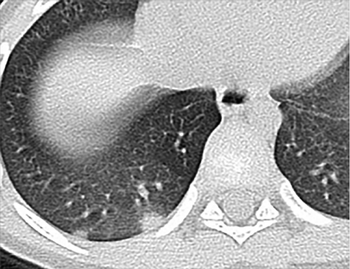

CT scan and video reveal peripheral, multilobar areas of ground-glass opacity.